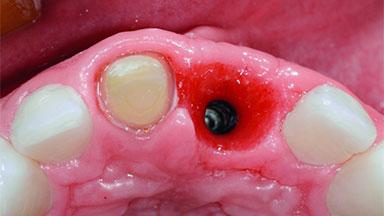

Replacement of an Ankylosed Upper Left Central Incisor: Bone Augmentation and Socket Grafting, Late Placement of an RC Bone Level Implant

# of Implants 1

Type of Implants Two-Piece

Bone Augmentation Horizontal|Simultaneous|Staged

Augmentation Materials Autogenous chips|Xenogenous